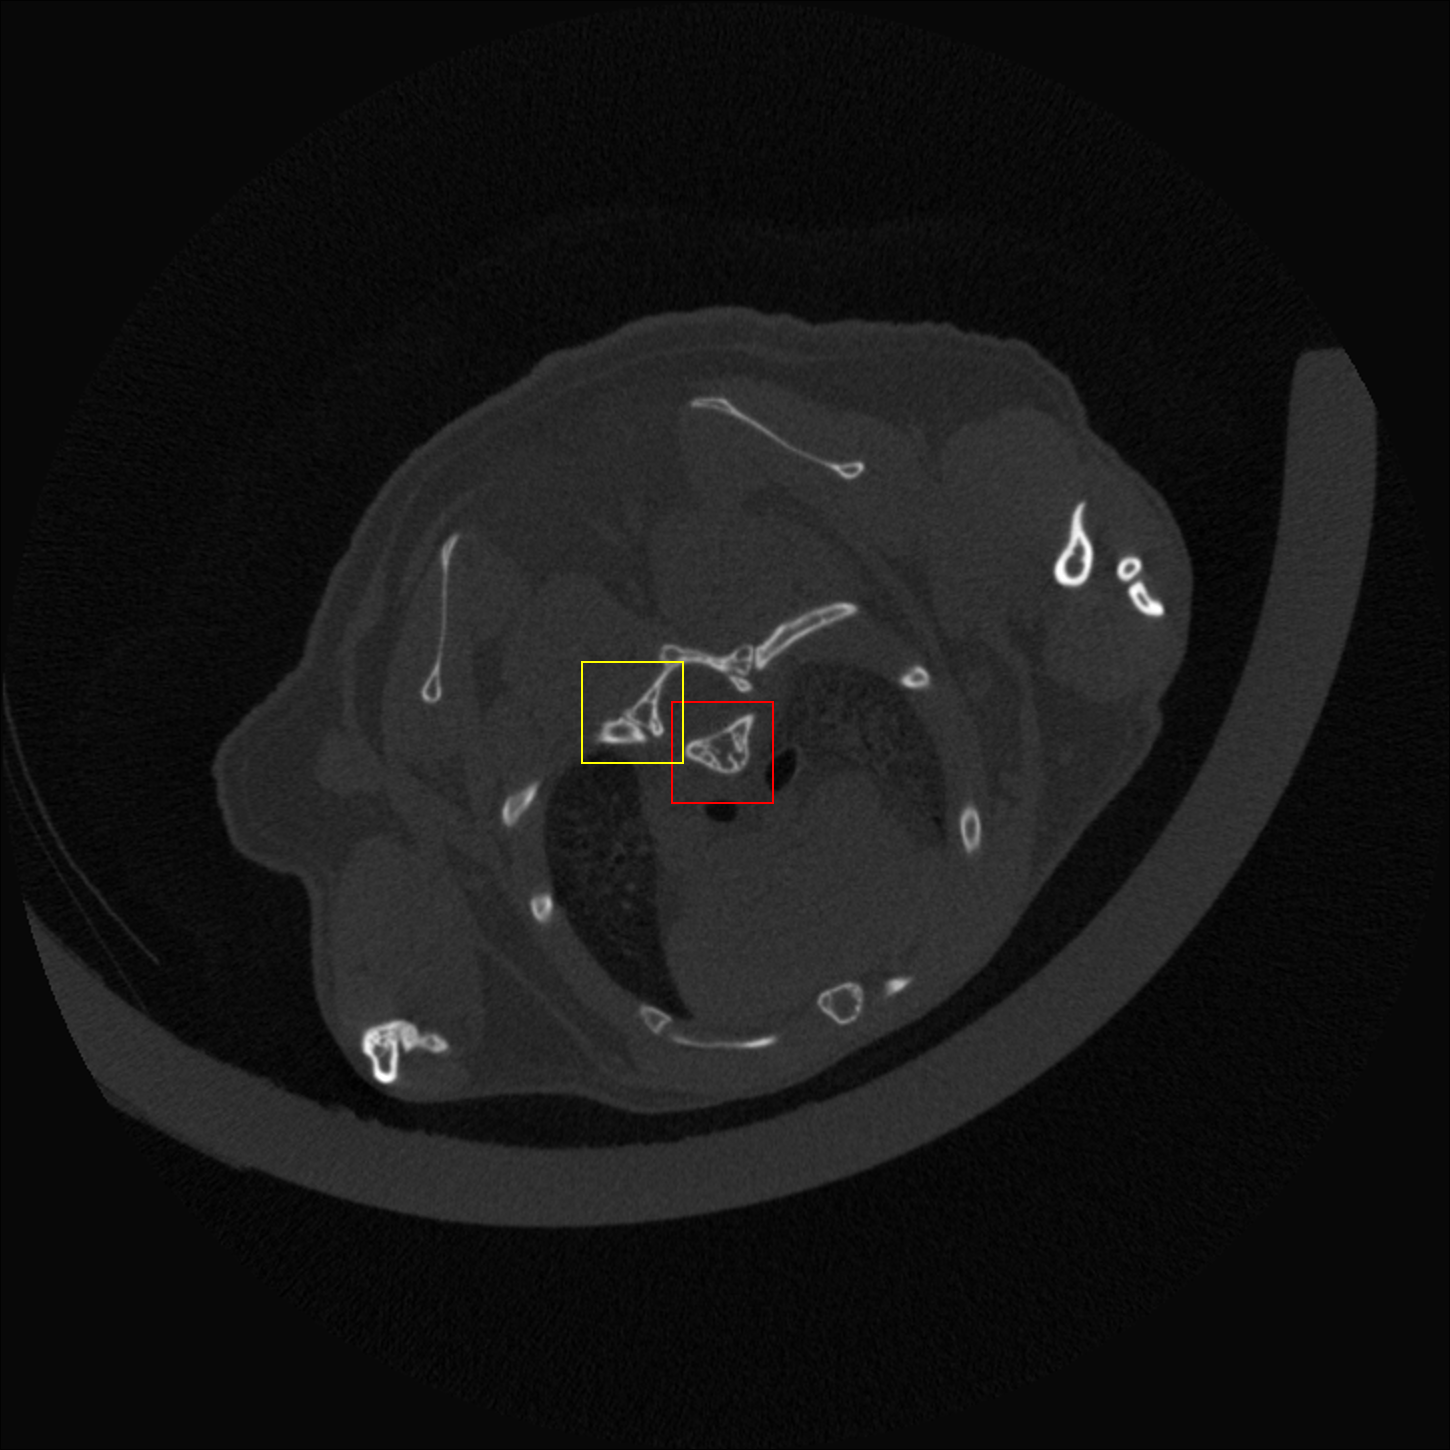

Figure 6: Visual comparison of SRCT Case 222 from the abdominal dataset. The display window is [-160, 240] HU. The restored anatomical features are shown in the red and yellow boxes. (Zoomed for visual clarity).

III-E Experimental Results on the Abdominal Dataset

We further compared the above-mentioned algorithms on the abdominal benchmark dataset. A similar trend can be observed on this dataset. Our proposed GAN-CIRCLE can preserve better anatomical informations and more clearly visualize the portal vein as shown in Fig. 6. These results demonstrate that PSNR-oriented methods (FSRCNN, ESPCN, LapSRN) can significantly suppress the noise and artifacts. However, it suffers from low image quality as judged by the human observer since it assumes that the impact of noise is independent of local image features, while the sensitivity of the Human Visual System (HVS) to noise depends on local contrast, intensity and structural variations. Fig. 6 displays the LRCT images processed by GAN-based methods (SRGAN, G-Adv, GAN-CIRCLE, GAN-CIRCLEs, and GAN-CIRCLEu) with improved structural identification. It can also observed that the GAN-based models also introduce strong noise into results. For example, there exist tiny artifacts on the results of GAN-CIRCLEu. As the SR results shown in Fig. 6, our proposed approaches (GAN-CIRCLE, GAN-CIRCLEs) are capable of retaining high-frequency details to reconstruct more realistic images with relatively lower noise compared with the other GAN-based methods (G-Adv, SRGAN). Table II show that G-Fwd achieves the best performance in PSNR. Our proposed methods GAN-CIRCLE and GAN-CIRCLEs both obtain the pleasing results in terms of SSIM and IFC. In other words, the results show that the proposed GAN-CIRCLE and GAN-CIRCLEs generate more visually pleasant results with sharper edges on the abdominal dataset than the competing state-of-the-art methods.